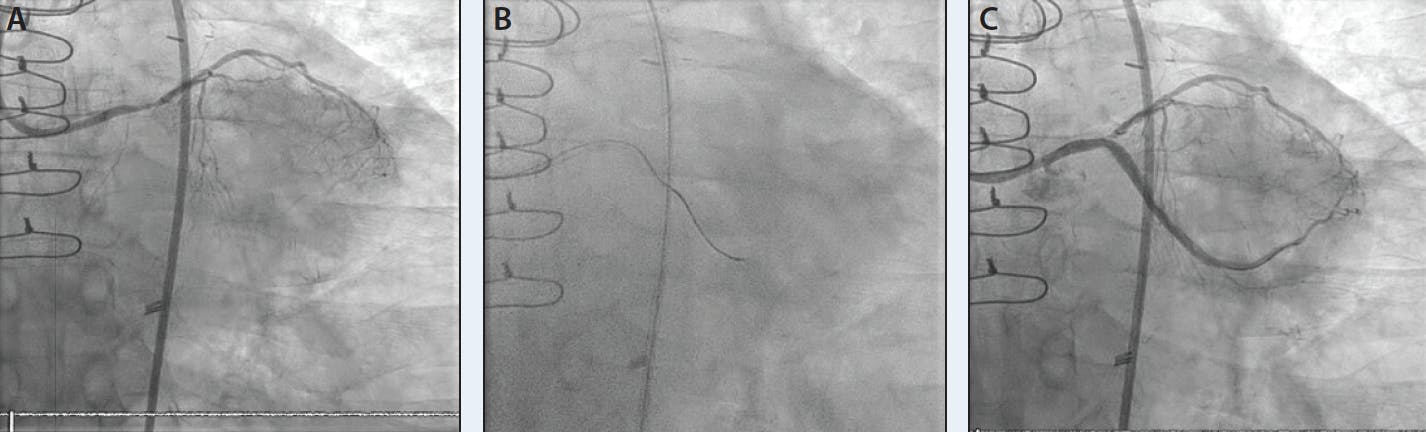

A CTO of the circumflex into the obtuse marginal is seen in Panel A and Video 1. Panel B demonstrates the microcatheter that was successfully advanced within the proximal CTO space; the wire was exchanged out for a Gladius Mongo wire. This wire was previously shaped into an umbrella bend and advanced out of the microcatheter tip. The wire immediately took on the desired/premade bend shape once leaving the microcatheter, after which it was advanced and jumped forward to reenter into the distal vessel. Panel C demonstrates the result after balloon angioplasty with a 2.5-mm balloon.